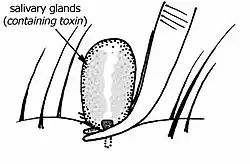

Toxins

It is thought the toxins of Ixodes holocyclus cause a failure of secretion of neurotransmitter acetylcholine at neuromuscular junctions. In experiments where nerve–muscle preparations were incubated in solution containing toxin, the paralysis effect was delayed for six to seven hours after the addition of toxin. As in live test animals, this effect was temperature dependent, paralysis being more rapid at higher temperatures. Live mice injected with toxin did not develop signs of paralysis for some 8 to 12 hours after the injection.[37] The cause of the delayed toxicity is unknown.[38]

Several toxic fractions have been isolated from the salivary glands of Ixodes holocyclus, but there has been variation in the reported molecular size of the principal paralysing toxin or toxins. Early work suggested that the most neurotoxic fraction was a protein (molecular weight 40–60 kilodaltons, stable when freeze dried, originally named holocyclotoxin).[39][40][41][42][43][44][45][46][47] Another toxin was found to be lethal but non-paralysing.[48]

A more recent study isolated three low-molecular-weight toxins, all three of which were able to cause hind limb paralysis in baby mice. Only one, however, could be isolated in quantities permitting further research. The molecule was relatively small at 6 kilodaltons, corresponding to a protein of approximately 50 amino acids like those in scorpion and spider toxins.[49][50][51]

The benefit conferred by the paralysing toxin is not clear. Being arachnids, ticks are related to predatory arthropods (spiders, scorpions and mites). Spiders and scorpions have retained toxins and developed specialised delivery structures (fangs and telsons) while mites and ticks have lost this feature. Of the 800 species of ticks, only 40–64 species (across 10 genera) have been reported as causing some form of toxicosis.[52][53][54][55] As ticks have moved from a predatory existence to a parasitic existence, most species have lost their toxin, which would have been a disadvantage for a parasitic lifestyle (parasites in general do not benefit from killing their hosts). The gene sequence of the tick toxin shows high homology to scorpion toxins.[56]

The saliva of Ixodes holocyclus also contains an anti-coagulant.[57]

Pets

Dogs and cats on the east coast of Australia commonly succumb to the tick paralysis caused by Ixodes holocyclus. A similar tick species, Ixodes cornuatus, appears to cause paralysis in Tasmania.[58] The paralyzing toxin (or toxins) is produced in the salivary glands and injected as part of the feeding process.